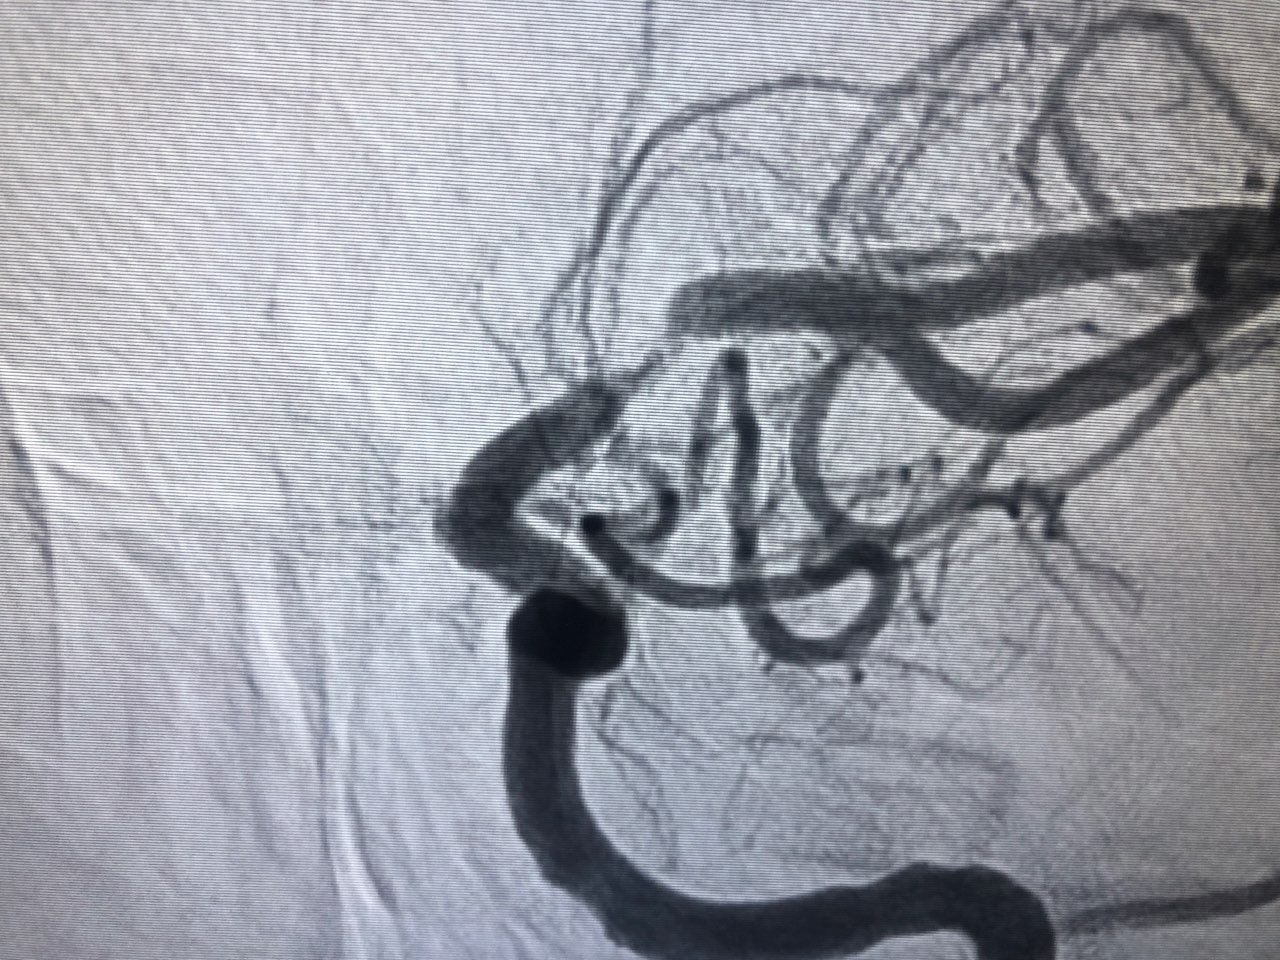

Pre-stent and post-stent images of blood flow (note the extremely limited blood flow – parts of the artery are nearly separated) in image 1 compared to image 2).

Angioplasty was not enough so they placed a 2mm x 8mm cobalt chromium stent. Dr. Perl looked extremely worried when I made a sound in response to the stent placement. After he finished he said “well it wasn’t your day to meet the celestial beings.” My speech immediately improved.

What I didn’t know is that Dr. Perl told Sara he did not expect me to survive. Blood flow was extremely restricted. I wish I could have spared Sara and Liz and all my loved ones the worry this caused.

Just after surgery Dr. Perl showed me images of my brain on his phone (the images at the beginning of this post). The next morning I asked him if he’d be willing to share the “super sexy pictures of my brain” and he texted me the images. This map of my stroke is based on those images:

Red areas show blood flow pre-stent. The small sliver of red in the center of the collapse shows the bridge of blood that kept me alive. Blue areas did not experience flow during the stroke. They are a catalogue of damage.